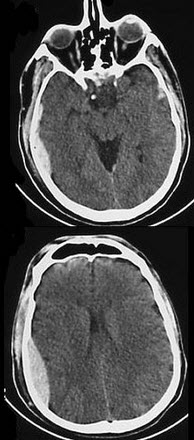

男,32岁,有头颅外伤史,结合CT图像选择最可能诊断( )

A:硬膜下血肿

B:硬膜外血肿

C:硬膜下积液

D:蛛网膜下隙出血

E:脑错裂伤